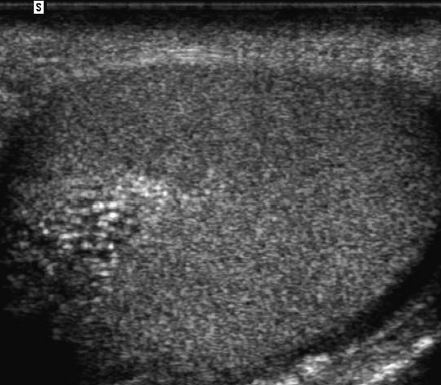

Testicular epidermoid cyst

• benign germ cell neoplasm

• monodermal teratoma - only ectodermal components

• appearance

• well-marginated lesoins that are typically hypoechoic

• hyperechoic rim with complete or partial rim of calcification

• onion ring/peel appearance